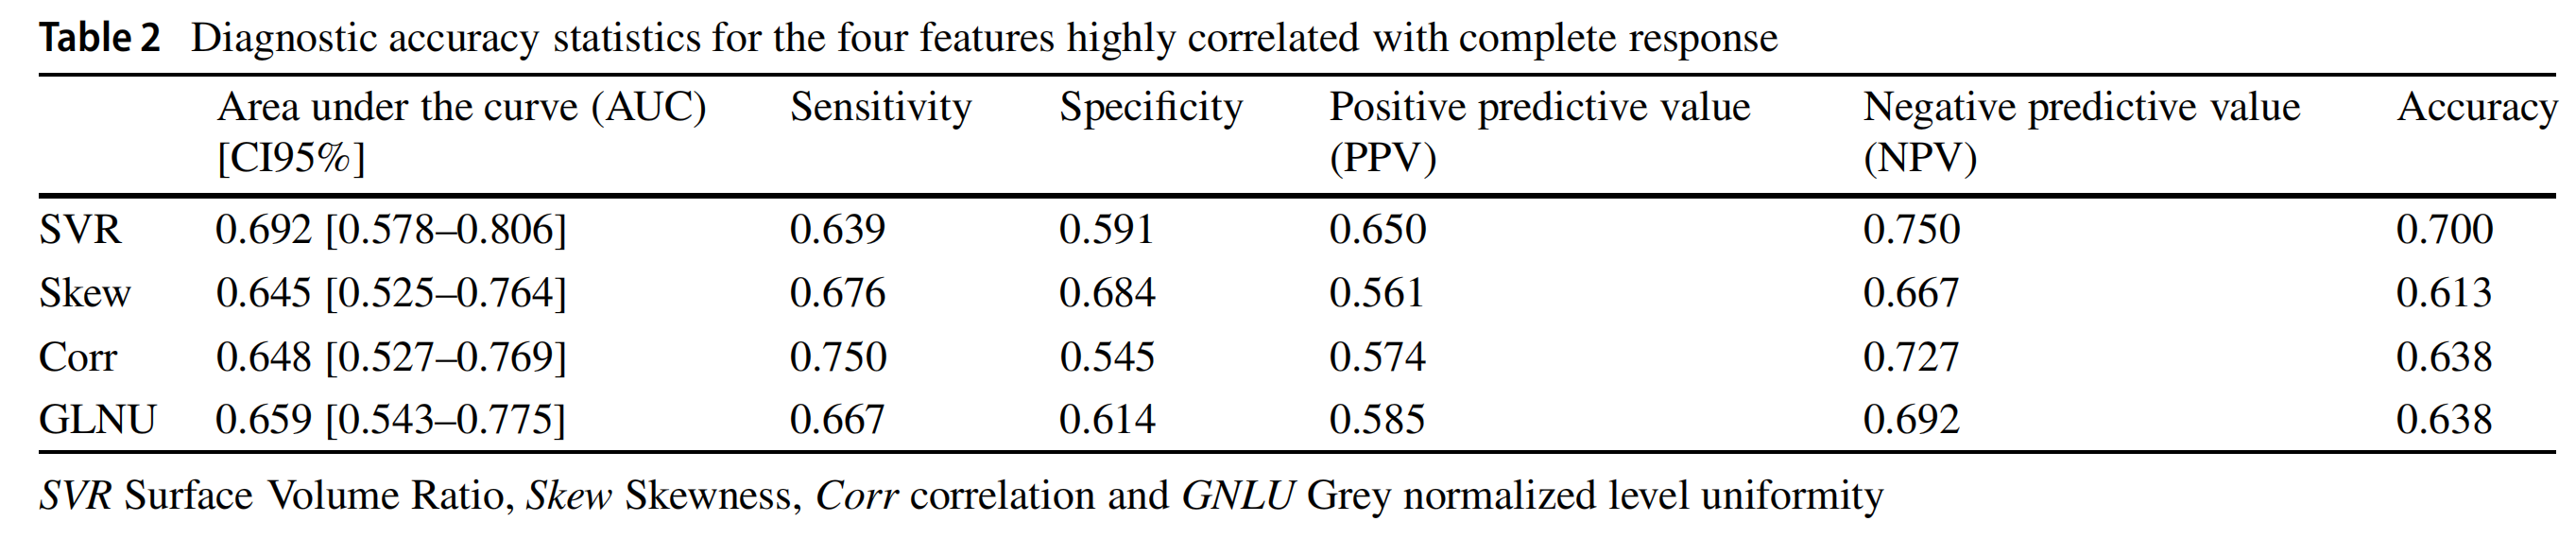

这四个放射组学特征与两组病变的关联在单变量分析(Mann–Whitney U检验)中报告了统计学意义(p< 0.05)。这些四个特征的详细诊断准确性统计数据在表2中报告,包括:

- 曲线下面积(AUC)

- 敏感性

- 特异性

- 阳性预测值

- 阴性预测值

- 准确度

尽管没有任何临床特征预示着完全缓解,我们发现四个放射组学特征(表面体积比、偏度、相关性和灰度非均匀性)与完全缓解显著相关,突出了放射组学分析在预测SBRT治疗后肺部转移瘤结果方面的潜力。

表面体积比是形状特征中与完全缓解相关性最高的。特别是,我们发现SVR值较高的病变在SBRT后有更高的完全缓解概率。这并不令人意外,因为已有充分报道指出,体积较大且不规则的肿瘤在总体生存和局部控制方面预后较差。有趣的是,偏度和相关性也在之前的放射组学研究中被确定为肺肿瘤的主要放射组学特征。

据我们所知,只有一项由Cheung等人[24]进行的研究评估了放射组学在预测SBRT治疗后肺寡转移瘤反应方面的作用。作者报告说,偏度和均方根是放射学治疗反应的预测因子,准确率为74.8%。另一方面,一些研究专注于将放射组学应用于原发性肺癌,以识别预测放射组学特征。例如,Bousabarah等人[22]报告了CT放射组学分析在110例不可手术的早期NSCLC患者中的应用,这些患者接受了SBRT治疗,旨在预测局部控制、总体生存和无病生存。具体来说,作者报告说,具有高偏度(即Hounsfield值较低的病变占主导地位)的肺肿瘤局部失败的风险较低,生存概率较高,而具有高相关性(组织同质性的度量)的肺肿瘤更可能导致局部失败。这些结果与我们发现的完全一致。